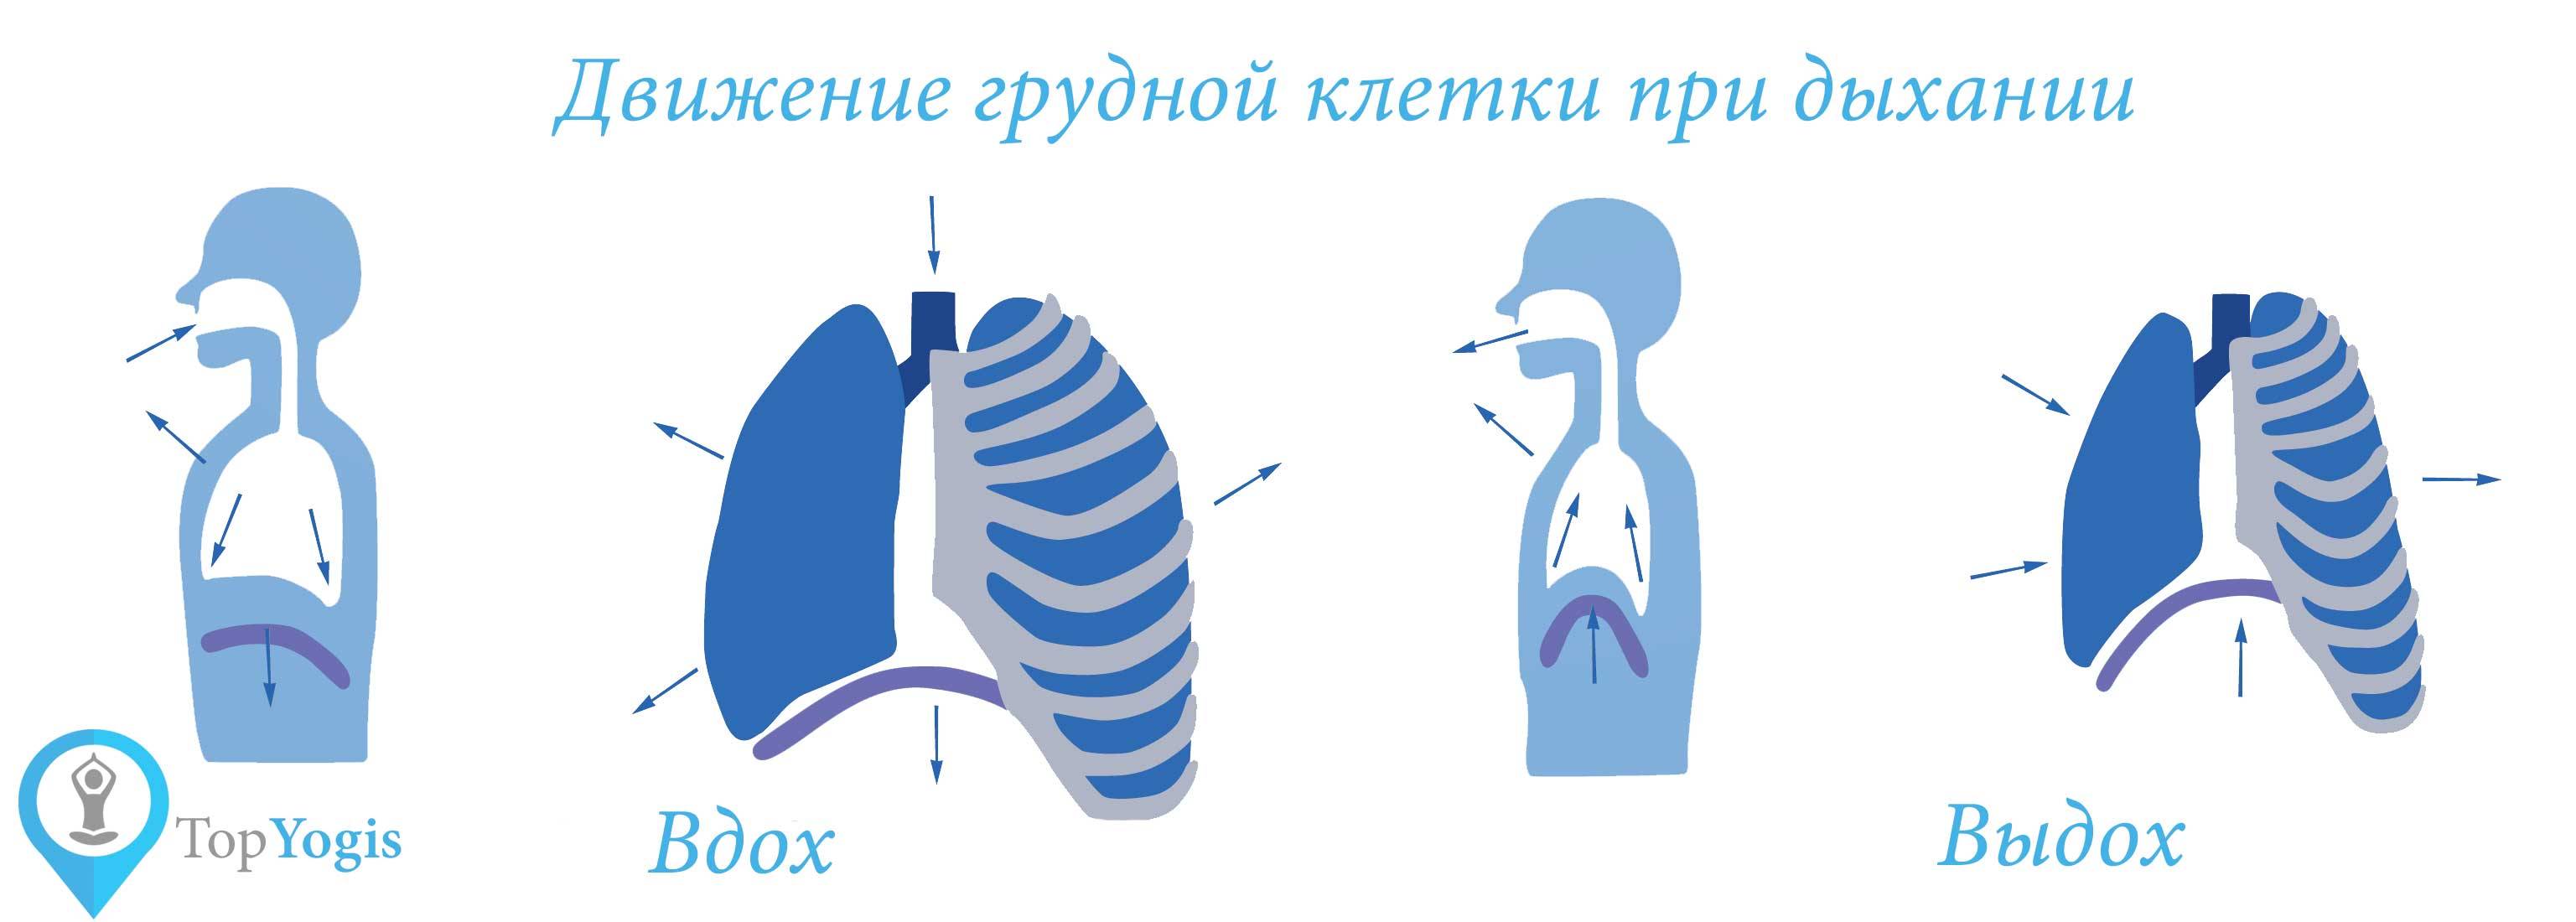

Что такое правильное дыхание

Чтобы понять, какое дыхание лучше – грудное или брюшное, следует изучить особенности движения элементов организма, которые отвечают за этот процесс. Считается, что дышать брюшным способом – лучше, чем грудным.

Чтобы понять, какое дыхание лучше – грудное или брюшное, следует изучить особенности движения элементов организма, которые отвечают за этот процесс. Считается, что дышать брюшным способом – лучше, чем грудным.

При любом типе дыхания за обработку кислорода отвечают легкие. Но их увеличение, как и изменение объема полости груди, зависит от 2 разных способов:

- При вдохе стенка груди приподнимается и отодвигается от позвоночника, из-за чего полость грудной клетки спереди увеличивается (образуется дополнительный объем между позвоночником и грудиной). В этом процессе участвуют ребра, прикрепленные к позвоночнику под острым углом. Своими концами они формируют дугу, расширяя возможный объем. Так как ребра крепятся к грудной кости, они тянут ее за собой.

- Второй способ зависит от опущения грудобрюшной преграды по направлению книзу. Это – диафрагма, имеющая куполообразную форму. Грудные мышцы отвечают в процессе дыхания за то, чтобы этот купол тянулся вниз, освобождая простор для легких. Середина опускается книзу и создается нужный объем. Из-за опущения грудная часть диафрагмы давит на живот, в результате выпячивается его стенка.

Первый тип дыхания называют грудным, а второй – брюшным. Считается, что мужчины дышат животом, а женщины – грудью. Связано это напрямую с особенностями и предназначением организма разных полов. Так как женщины во время беременности не могут полноценно дышать животом, природа предусмотрела для них другой вариант – грудной способ дыхания. У мужчин такого препятствия нет, поэтому они дышат животом.

Первый тип дыхания называют грудным, а второй – брюшным. Считается, что мужчины дышат животом, а женщины – грудью. Связано это напрямую с особенностями и предназначением организма разных полов. Так как женщины во время беременности не могут полноценно дышать животом, природа предусмотрела для них другой вариант – грудной способ дыхания. У мужчин такого препятствия нет, поэтому они дышат животом.